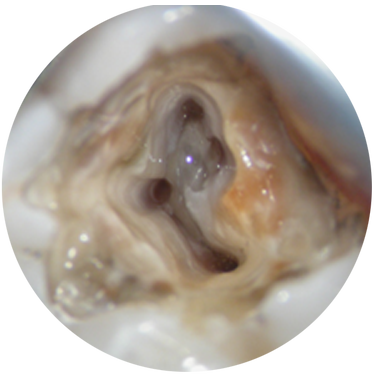

What’s the best way to irrigate the canal? What are the advantages of bioceramic-based products in obturation techniques? This program will review some basic principles of cleaning, shaping, and obturation, with a look at some new and clinically proven products and techniques.